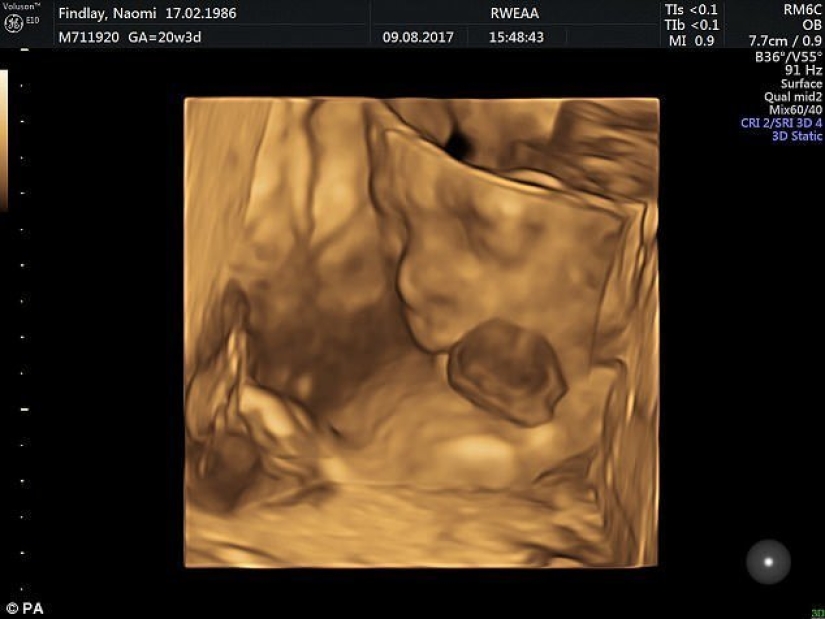

The girl's parents found out about ectopia in the ninth week of pregnancy, but the mother refused to have an abortion, despite the persuasions of doctors.

According to the results of the tests, the baby had no chromosomal abnormalities. The specialists decided to direct all their efforts to save the child. Then a large team of obstetricians, neonatologists, cardiologists and other specialists was assembled.